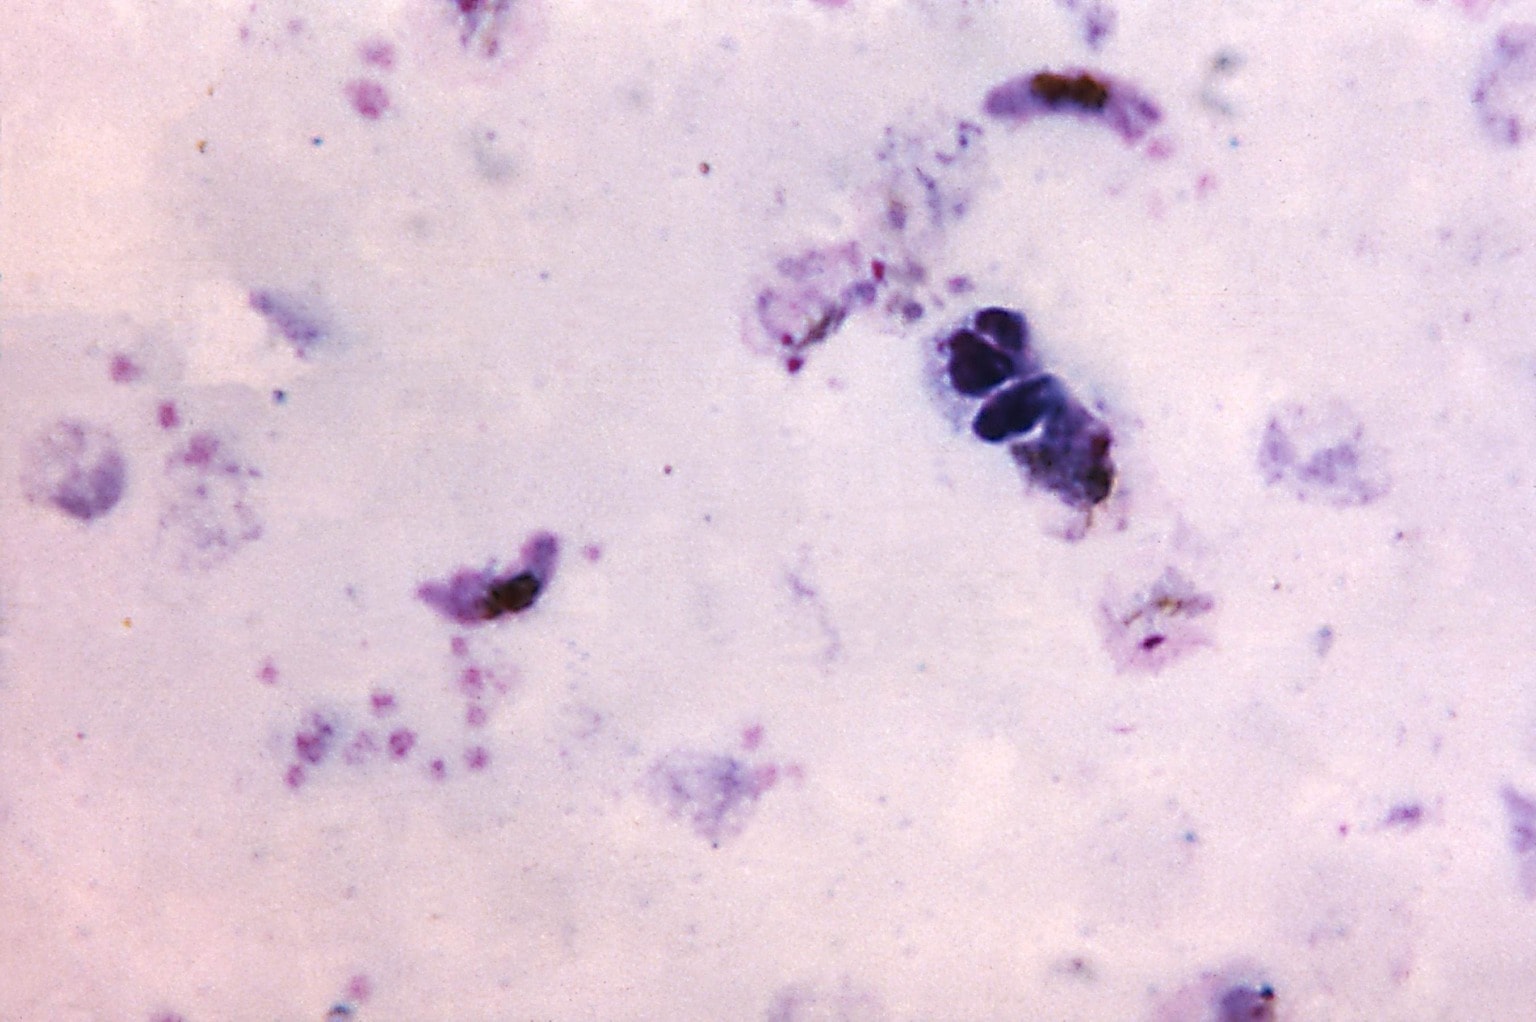

Структура клеток: Эктоплазма и цитоплазма в научных изображениях

Раздел: Галерея прозрений